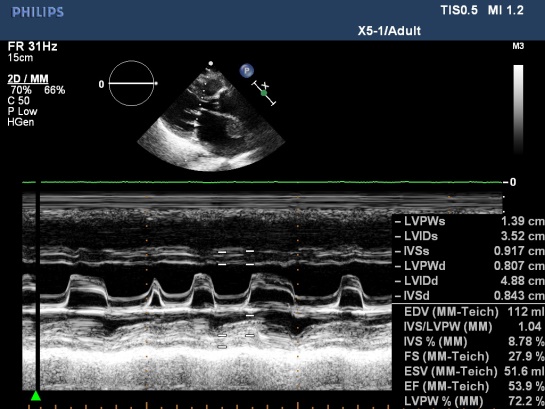

Figure 5. MS with AF, M-mode TTE; “M –mode TTE image from Nguyen Tuan Vu”

Atrial Fibrillation: Atrial fibrillation (AF) is the most common cardiac arrhythmia, with prevalence of 1 % in the general population and increasing with age [8]. The incidence of stroke in atrial fibrillation patients is about from 2 to 10.5% per year depending on risk factors [9,10] including LA enlargement [11].

This arrhythmia is the most important resource responsible for 45% of cardioembolic stroke in Western countries [12] but in our data the rate is 25%.

TTE evaluates size and function of cardiac chambers, associated cardiac lesions such as valvular heart diseases, pericardial abnormalities. TEE evaluates size and morphology of LAA, velocity of LAA blood flow, identifies and excludes spontaneous contrast and thrombus of LAA and LA.